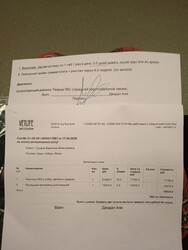

24 апреля мы поехали домой! В смысле в приют, который Шура считает своим домом, пока другого ей никто непредложил. Счёт за дни в Юне с 21 по 24 апреля на сумму 8163,83 ниже

Наконец то свели все цифры по затратам на операцию для Шурочки:

РАСХОД:

-Ветлайф 52965

-лекарства 8116

-Юна 27168,81

————————

Всего 88 249,81₽

СПАСИБО ОГОРОМНОЕ всем, кто помогает.    Вся сумма, потраченная на операцию Шуре, собрана, долги закрыты! Вся сумма, потраченная на операцию Шуре, собрана, долги закрыты!